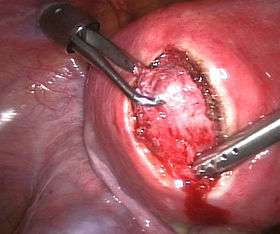

A relatively large submucosal leiomyoma; it fills out the major part of the endometrial cavity